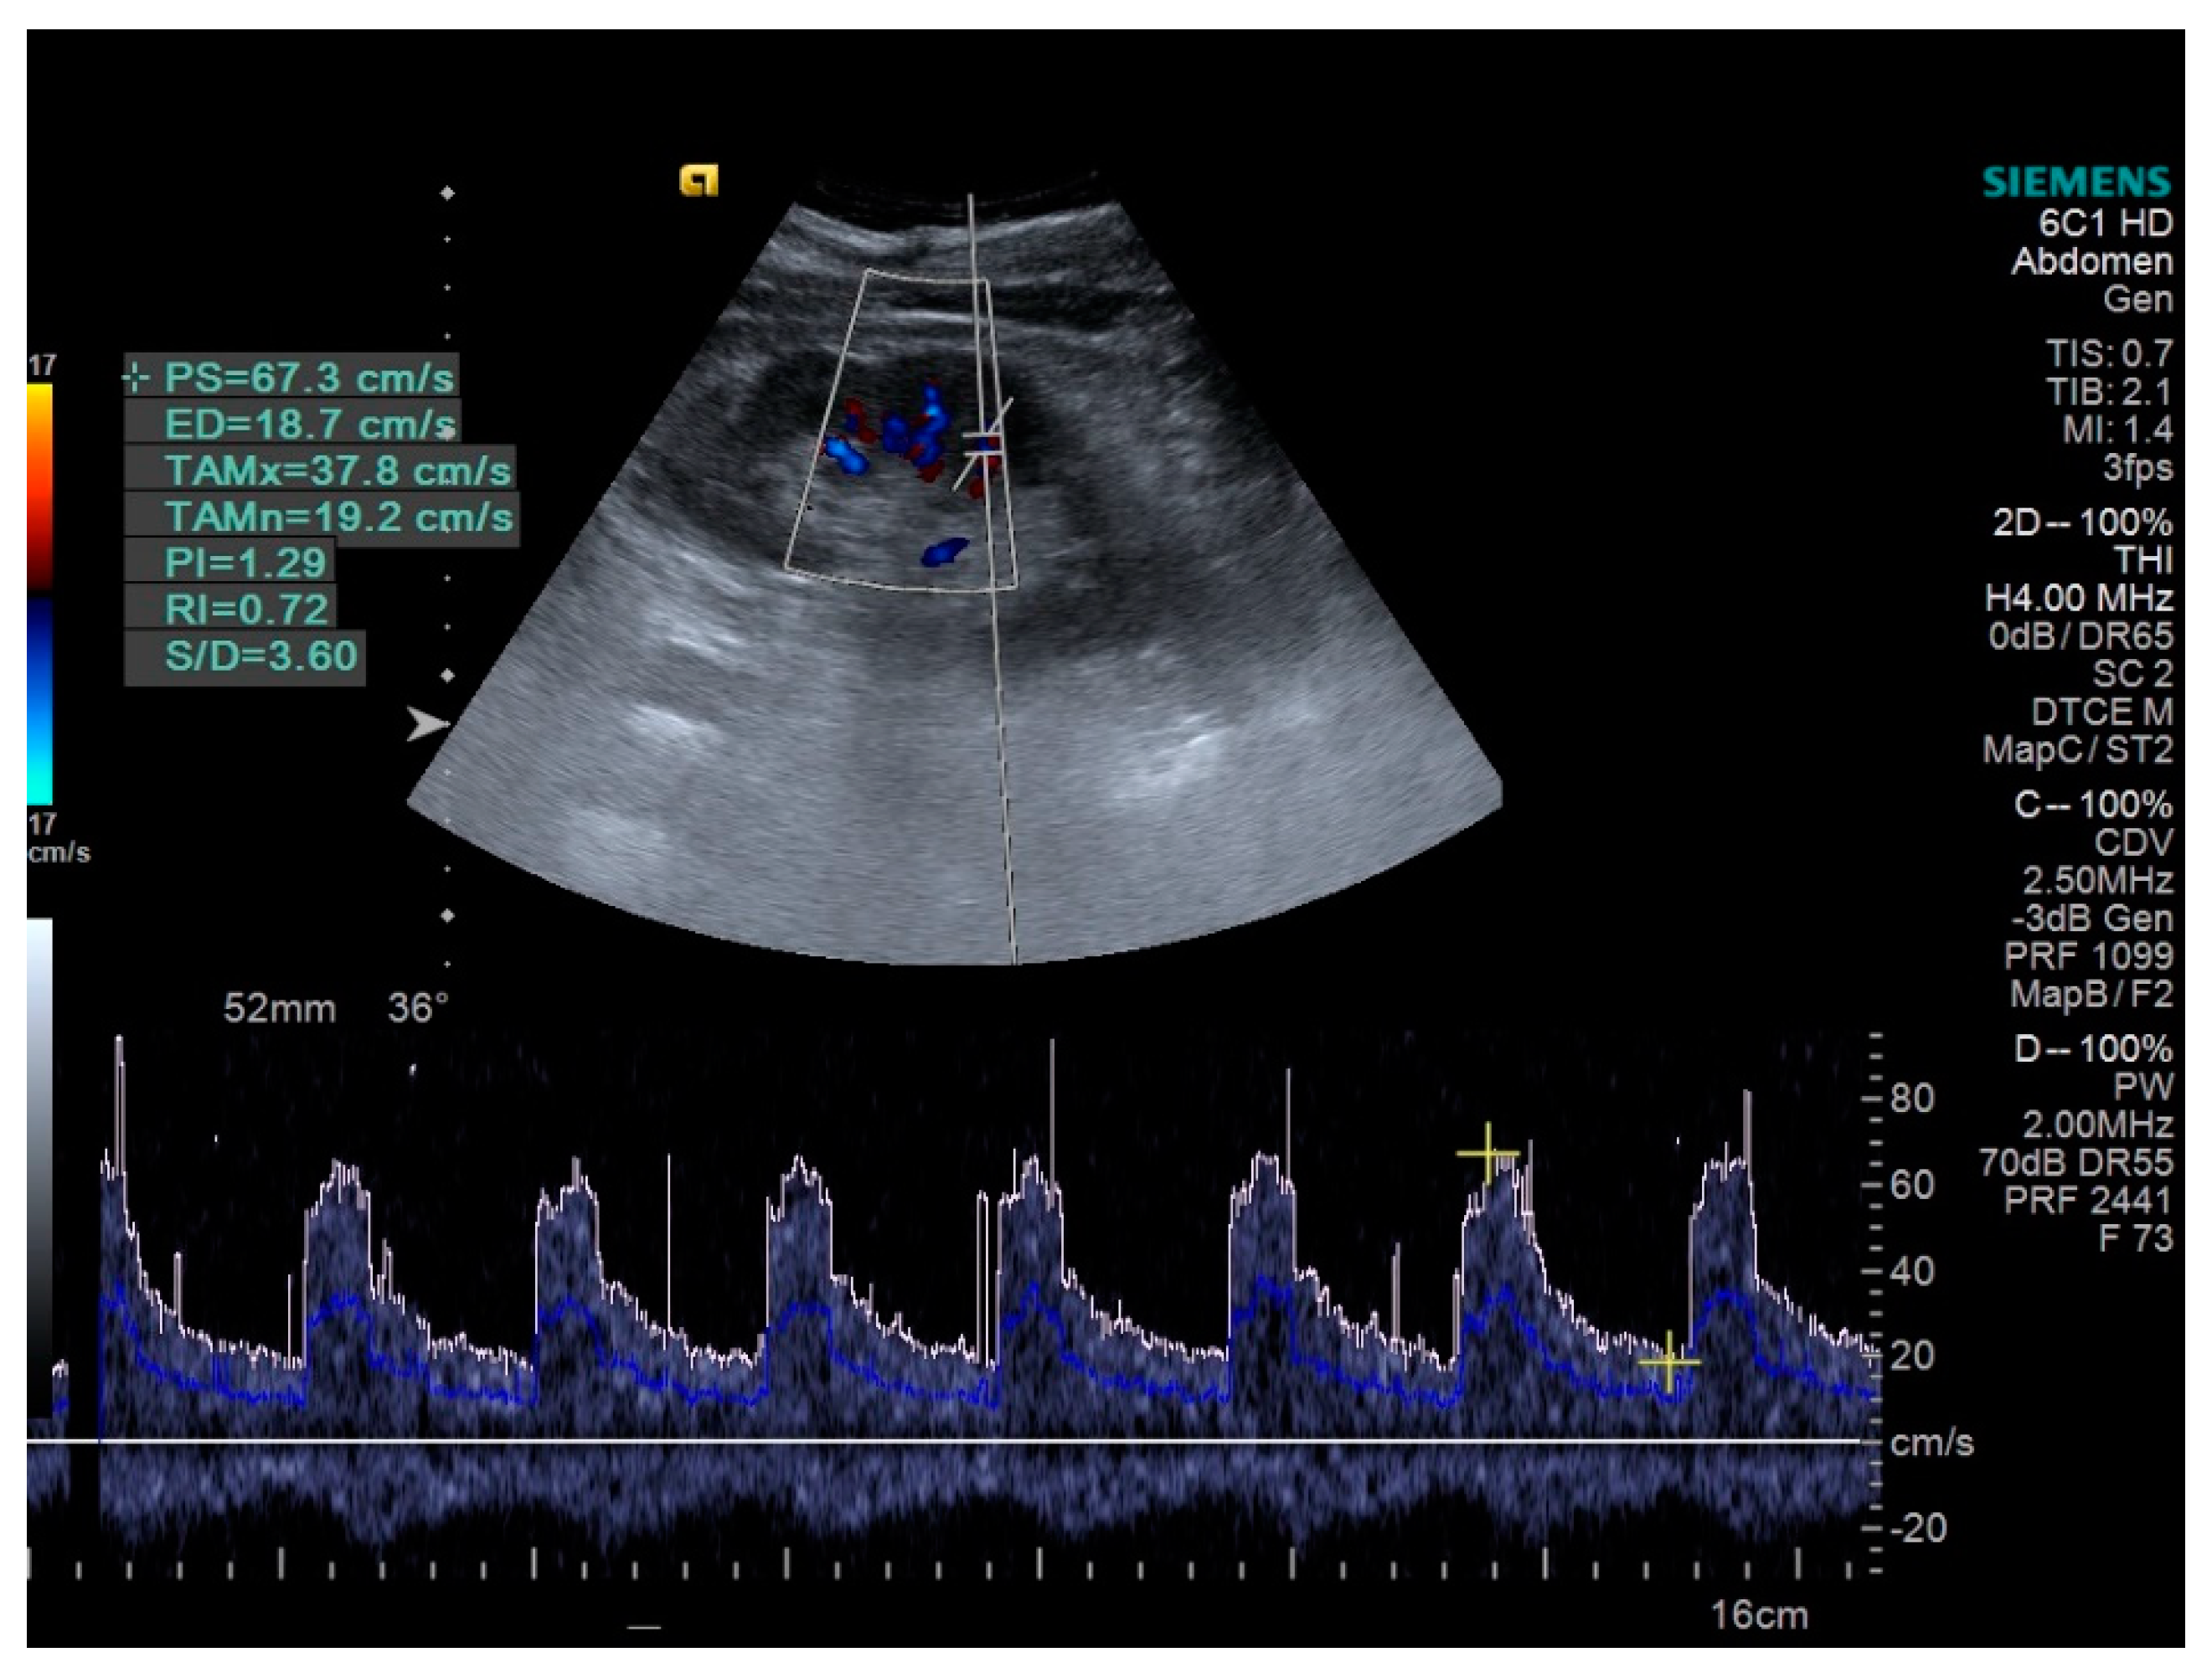

The histological abnormalities are responsible for the changes of the monitored parameters. Intrarenal parenchyma arteries show progressive intimal thickening, afferent arterioles present a process of arteriosclerosis, all these changes being highlighted by the increase of RRI (Figure 1). Another factor responsible for the RRI increased is tubular atrophy associated with interstitial fibrosis [9,20,21]. Glomerular involvement is expressed by UACR increasing [9]. But the kidney is a complex organ and the SWV, as a marker of its stiffness, is dependent on the degree of renal fibrosis, as well as on the intrarenal vascularization [22] (Figure 2).

This study identified that the RRI were higher in HN patients than in controls (0.72 ± 0.02 in HN patients versus 0.63 ± 0.02 in controls, p < 0.0001). In a group of 211 patients with essential hypertension, higher RRI of interlobar renal arteries was associated with higher prevalence of microalbuminuria (p = 0.008) [29]. In another study, Doi et al. demonstrated that the increased RRI was associated with low eGFR, this association being related with poor cardiovascular and renal outcomes. [30]. Elevated RRI values were associated with increased UACR and decreased eGFR (p < 0.01) [20].

Figure 1. Interlobar renal artery (RRI = 0.72).